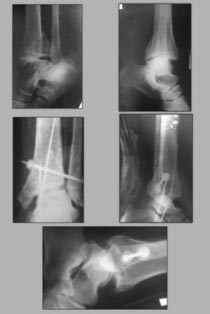

Больной Г. 1960г.р. Травму получил 2 месяца тому назад, прооперирован в

областной клинике.

Сейчас удалены трансартикулярные спицы. Снята гипсовая повязка. В обл.

голеностопного сустава отёк держится. У меня возникли вопроси в

правильности проведенной операции.Прошу вашего совета. Рентген снимок

прилагается.